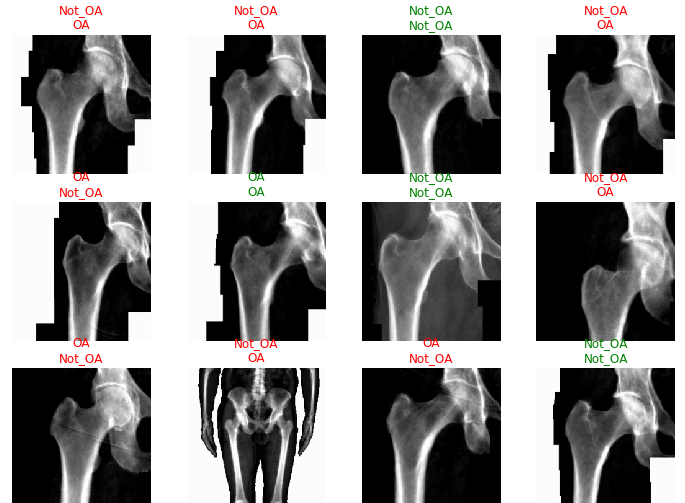

#learn.show_results(max_n=32, nrows=8)

#interp = ClassificationInterpretation.from_learner(learn)

What Went Wrong

Clearly, the classifier did not have a very high accuracy in determining hip OA based on hip X-rays. However, any trained doctor is generally able to diagnose hip OA based upon X-rays alone. One extremely noteable source of errors lies in the fact that the metadata obtained for each patient did not specify which hip had OA. OA typically only presents itself in a single hip for each patient, and without that information, some of these hip X-rays were misleading as they could be fully healthy and not the correct hip. Furthermore, it is possible that this image classification is not as overt as we originally thought. However, that does not explain the extremely low accuracy that my classifier generated after training.